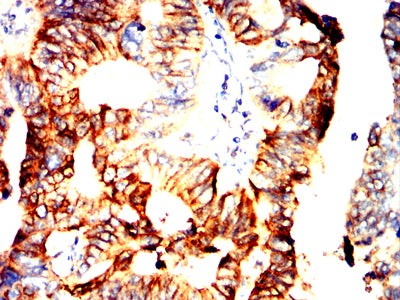

Immunohistochemical analysis of paraffin-embedded human kidney cancer tissues using RUFY4 mouse mAb with DAB staining

Immunohistochemical analysis of paraffin-embedded human rectum cancer tissues using RUFY4 mouse mAb with DAB staining